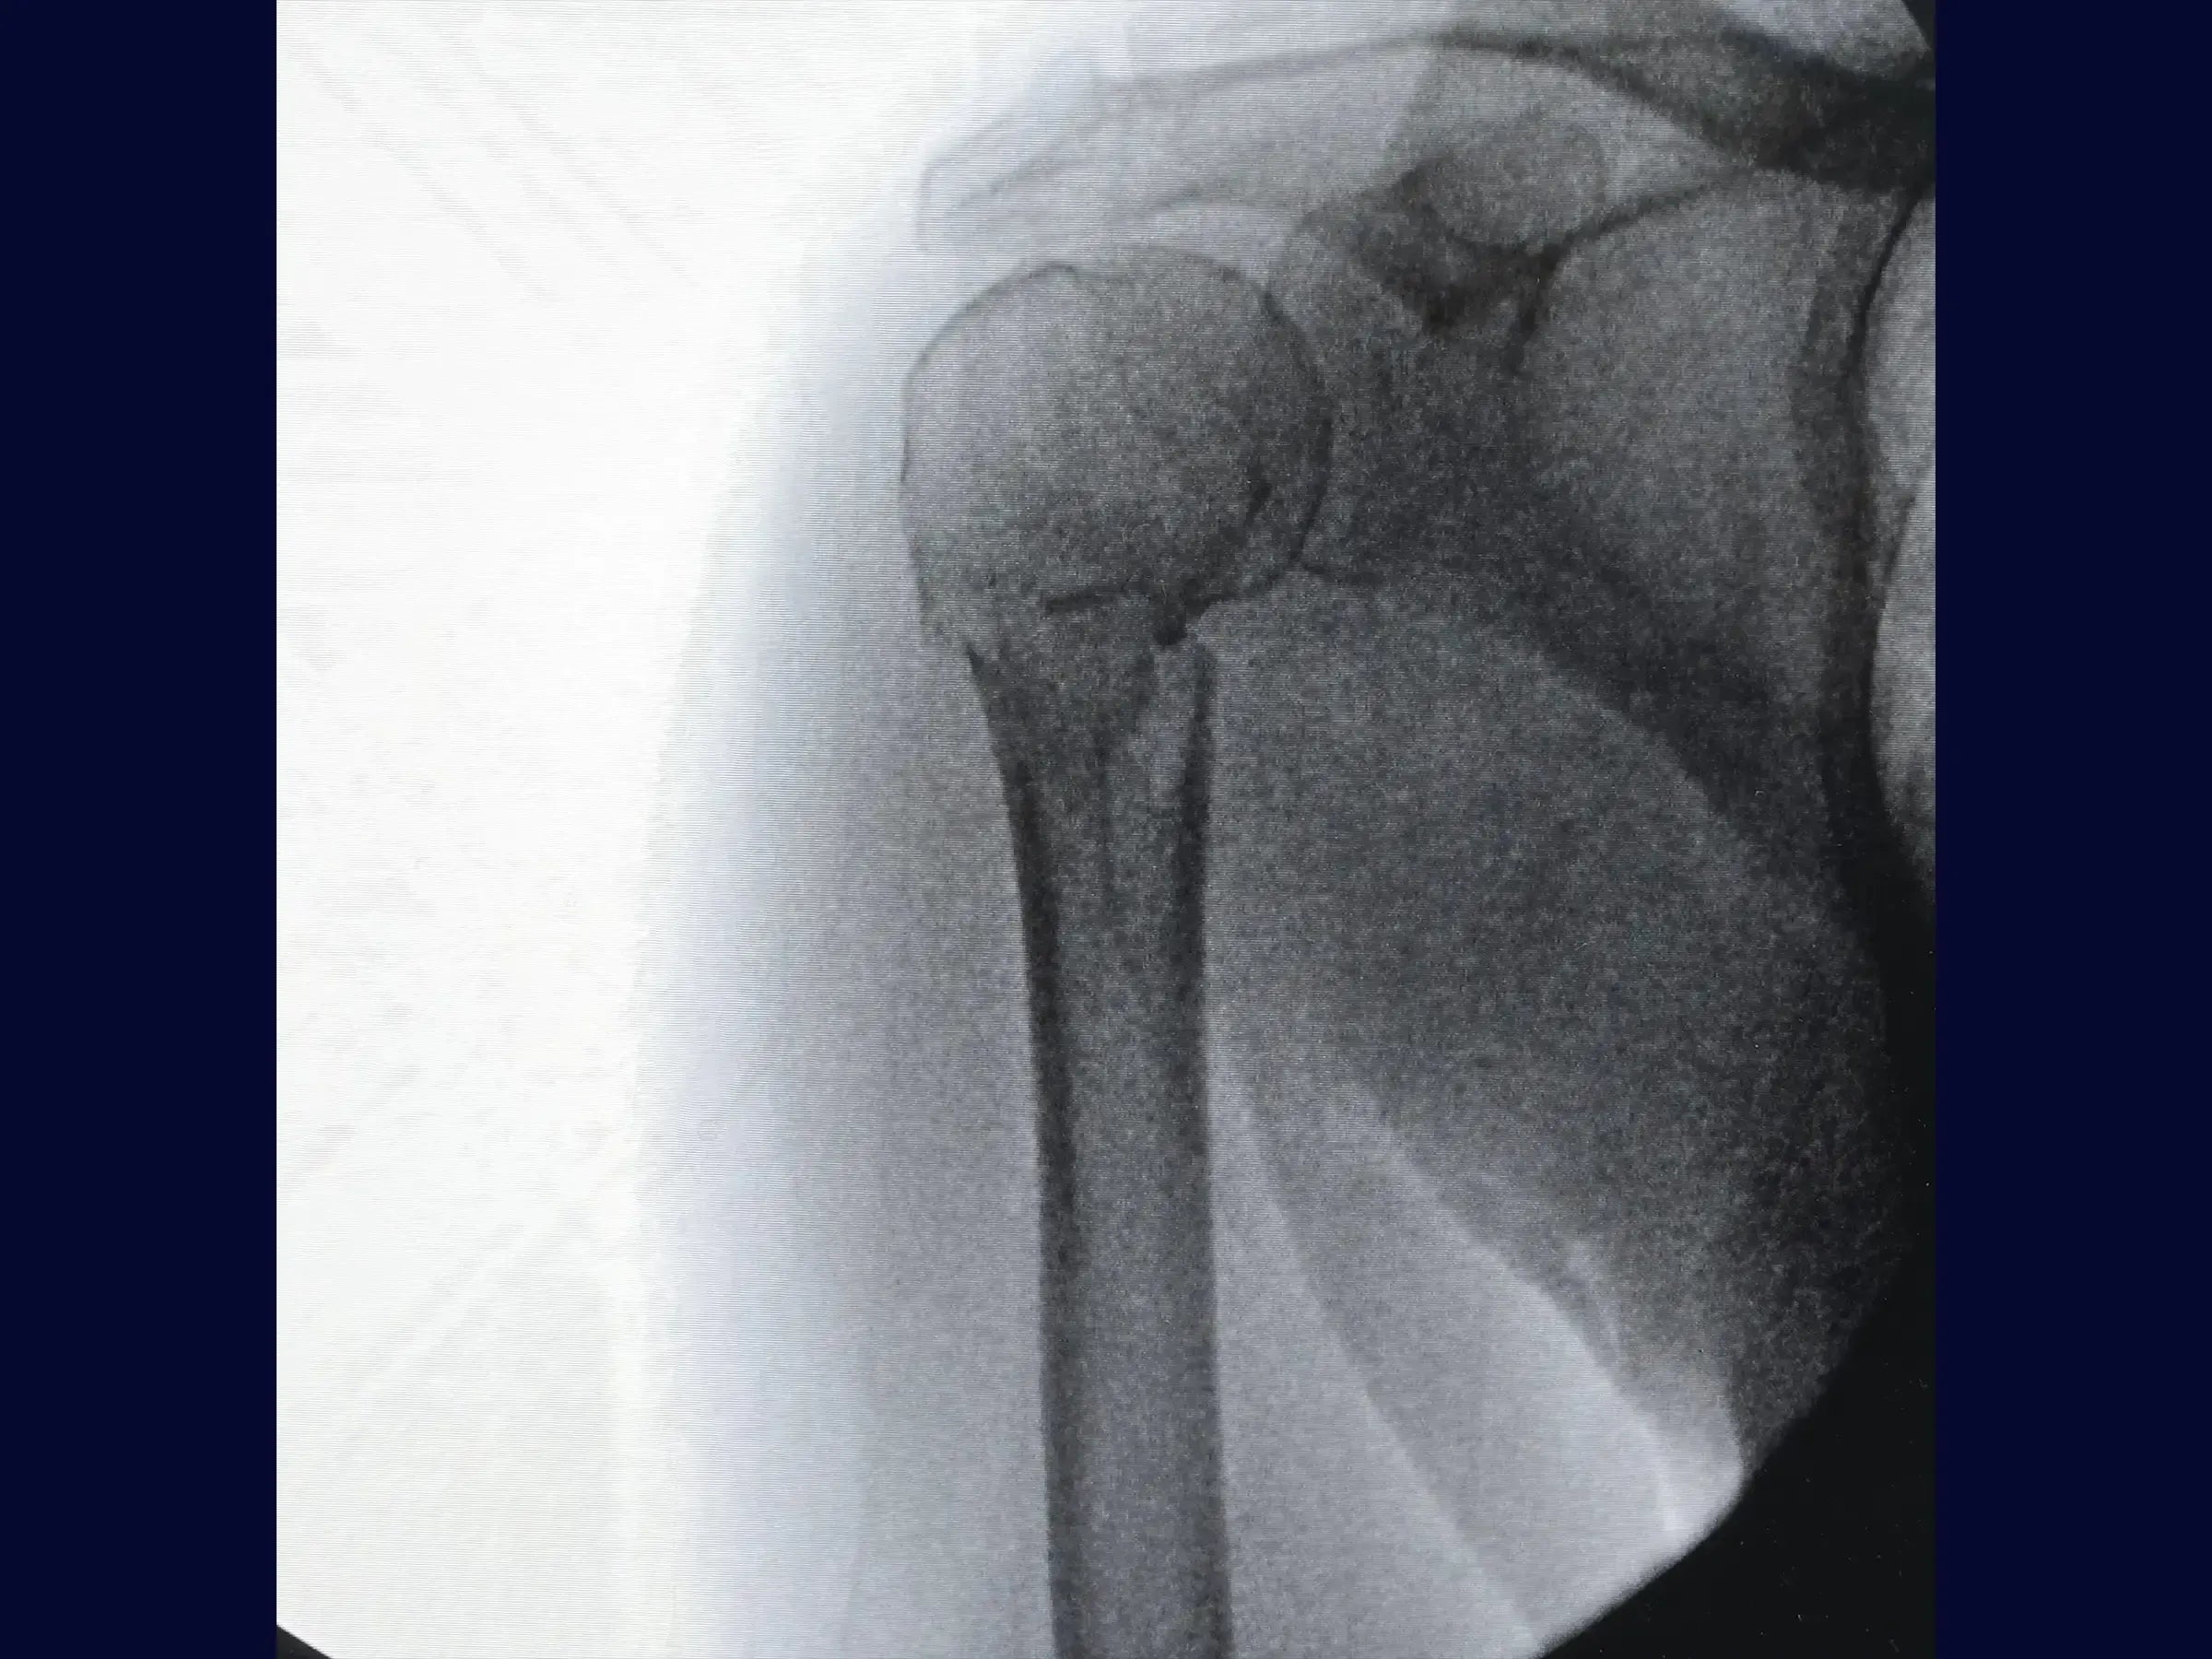

Master the treatment of proximal humerus fractures in 2 parts. This training offers a technical immersion in the deltopectoral approach for osteosynthesis, presented in 4K video from the surgeon's perspective, detailing each step of the procedure to optimize results.

- Anatomical reduction of proximal humerus fractures and provisional fixation.

- Manoeuvres for valgization of the humeral head.

- Refined Anatomical Reduction: Protocols for cleaning fracture vertices, identifying parameters such as the bicipital groove, and efficient provisional fixation.

- Correction of Varus: Specific maneuvers (abduction, traction with high-resistance wire, thumb pressure, and inverted condylar grip) for valgization of the humeral head.